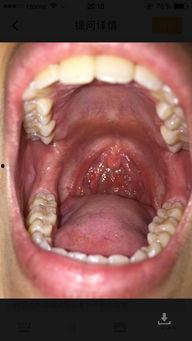

吃白瓜喉咙疼,揭秘原因及应对策略

最近天气热得让人受不了,你是不是也和我一样,整天想着吃点清凉解暑的东西呢?不过,你知道吗?有些食物虽然看起来很清爽,但吃下去却可能让你喉咙疼得要命。今天,我就要和你聊聊这个让人头疼的问题——吃白瓜喉咙疼。白瓜,又称黄瓜,是一...